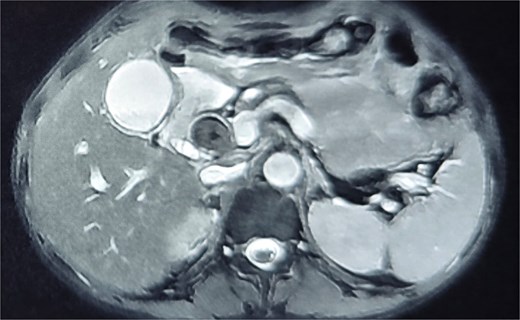

A 41-year-old man with diabetes was admitted to the gastrointestinal (GI) surgery ward with a 12-day history of abdominal pain and vomiting in June 2025. On examination, the patient was pale and dehydrated but hemodynamically stable, with tenderness in the right hypochondrium. All laboratory results were within normal limits, except for elevated alkaline phosphatase (520 U/l) and random blood sugar levels. Abdominal ultrasound revealed acute calculus cholecystitis, choledocholithiasis (13.2 mm stone), and a dilated CBD with intra-hepatic biliary radicals dilatation (IHBRD). Magnetic resonance cholangiopancreatography (MRCP) confirmed cholelithiasis, acute cholecystitis, choledocholithiasis, and dilated CBD (3 cm) with central IHBRD with no suspicion of biliary stent (Fig. 1).

Magnetic resonance cholangiopancreatography (MRCP) confirmed cholelithiasis, acute cholecystitis, choledocholithiasis, and dilated CBD (3 cm) with central IHBRD with no suspicion of biliary stent.